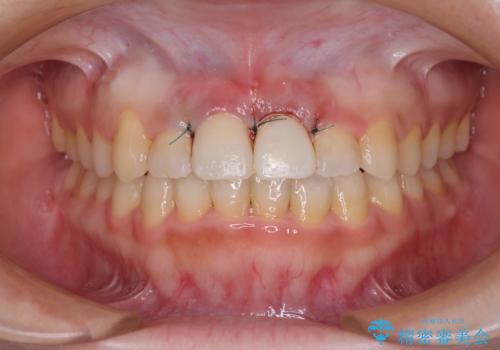

変色してしまった前歯は、反対側の歯と比べて歯肉が覆い被さっていたため、骨整形を含めた歯周外科処置を行い、歯肉ラインを整えることとしました。

歯周外科処置を行うかどうかは非常に悩んでいらっしゃいましたが、範囲がそれほど広くないため術後の痛みも強くないだろうということで、処置を行うこととなりました。